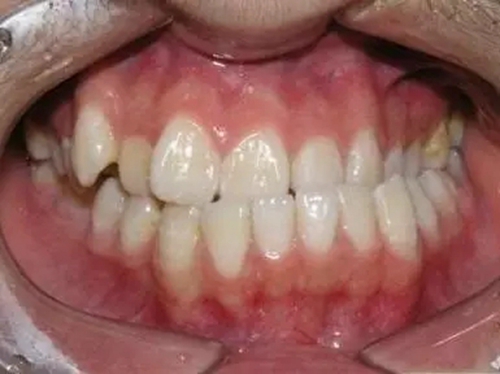

1、錯合畸形、咬合關(guān)系紊亂

由于反復向一側(cè)運動,使下前牙的正中線向一側(cè)錯位從而導致后邊的牙齒形成刃對刃、尖對尖的咬合,甚至反咬合(下牙包上牙)。